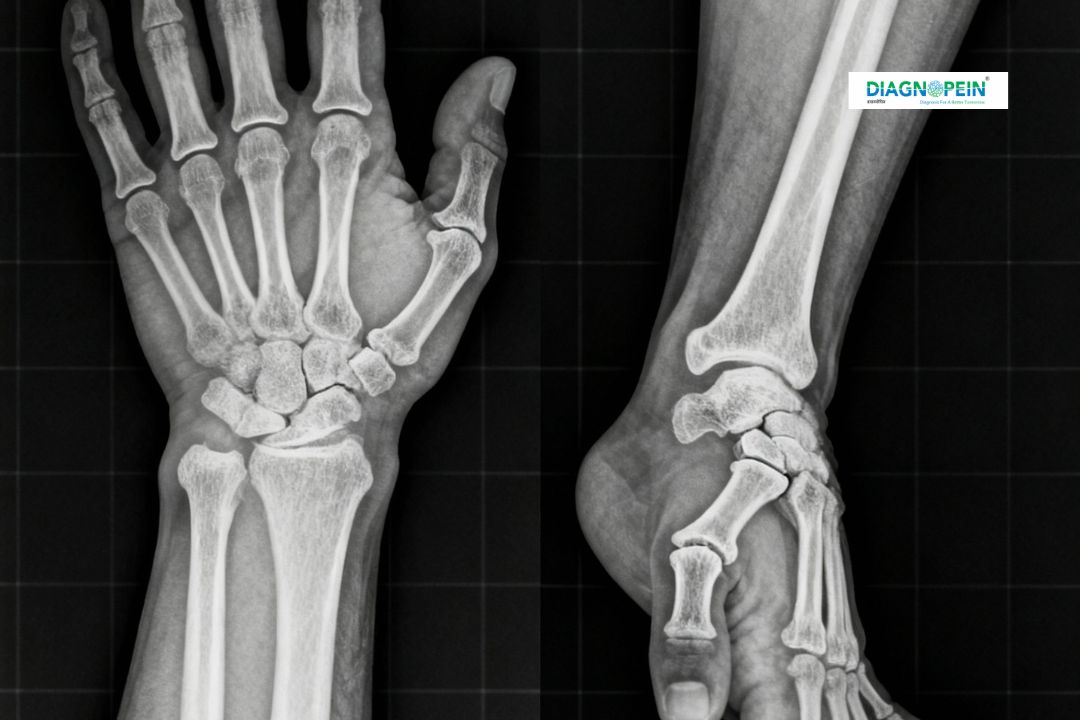

The X-Ray Both Wrist AP/Lat is a diagnostic imaging test that captures two standard views of the wrists — the AP (front to back) and the Lat (side) views. These views provide a complete image of wrist bones, joints, and soft tissue alignment, enabling accurate diagnosis of conditions such as fractures, arthritis, bone deformities, and post-surgical assessments.

At Diagnopein in karad, the test is performed using low radiation digital X-ray systems, which provide fast image output and enhanced clarity while minimizing exposure. It is commonly recommended for patients who experience wrist pain, swelling, suspected fractures, stiffness, or sports injuries.

2. The technician positions both wrists on the X-ray plate – first for the AP (front) view and then for the Lateral (side) view.

3. The machine captures high-resolution images in both positions.